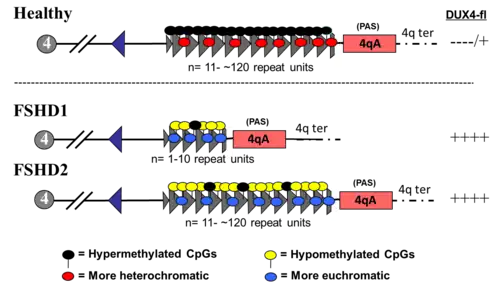

The genetics of FSHD are complex.[2] FSHD and the myotonic dystrophies have unique genetic mechanisms that differ substantially from the rest of the genetic myopathies.[49] The DUX4 gene is the focal point of FSHD genetics. Normally, full-length DUX4 protein (DUX4-fl) is expressed during early embryogenesis, in testicular tissue of adults, and the thymus; in all other tissues, it is repressed.[50] In FSHD, within muscle tissue there is a failure of DUX4 repression and continued production of DUX4-fl protein, which is toxic to muscles.[2][8][50] The mechanism of failed DUX4 repression is hypomethylation of DUX4 and its surrounding DNA on the tip of chromosome 4 (4q35), allowing transcription of DUX4 into messenger RNA (mRNA). Several mutations can result in disease, upon which FSHD is sub-classified into FSHD type 1 (FSHD1) and FSHD type 2 (FSHD2).[27] Disease can only result when a mutation is present in combination with select, commonly found variations of 4q35, termed haplotype polymorphisms, which are roughly dividable into the groups 4qA and 4qB.[51] A 4qA haplotype polymorphism, often referred to as a 4qA allele, is necessary for disease, as it contains a polyadenylation sequence that allows DUX4 mRNA to resist degradation long enough to be translated into DUX4 protein.[8]

DUX4 resides within the D4Z4 macrosatellite repeat array, which is a DNA sequence composed of a variable number of tandemly repeated large DNA segments (ie, repeats). The D4Z4 repeat array is located at the tip of the large arm of chromosome 4, abbreviated as '4q35'.[52] Each D4Z4 repeat is 3.3 kilobase pairs (kb) long and is the site of epigenetic regulation, containing both heterochromatin and euchromatin structures.[53][54] In FSHD, the heterochromatin structure is lost, becoming euchromatin,[53] which consists of less methylation of DNA, and altered methylation of histones.[55] Histone methylation patterns differ slightly between FSHD1 and FSHD2.[55]

The subtelomeric region of chromosome 10q contains a tandem repeat structure highly homologous (99% identical) to 4q35,[8][51] containing "D4Z4-like" repeats with protein-coding regions identical to DUX4 (D10Z10 repeats and DUX4L10, respectively).[8][56] Because 10q usually lacks a polyadenylation sequence, it is usually not implicated in disease. However, chromosomal rearrangements can occur between 4q and 10q repeat arrays, and involvement in disease is possible if a 4q D4Z4 repeat and polyadenylation signal are transferred onto 10q,[57][8][58] or if rearrangement causes FSHD1.

D4Z4 repeat array types are subclassified into 4qA and 4qB alleles, with only 4qA alleles causing disease. 4qA alleles are defined by a specific sequence of DNA immediately downstream to the D4Z4 repeat array: a 260 base pair region named pLAM, followed by a 6,200 base pair beta satellite region.[9][59] 4qA and 4qB alleles, together, can be subdivided into at least 17 types,[51] based on the DNA upstream from the D4Z4 repeat array, the presence/absence of restriction enzyme sites within D4Z4, the size of the last D4Z4 repeat element, and the DNA present downstream to the D4Z4 repeat array.[59] For example, the most common 4qA allele, 4A161, has 161 nucleotides in the region upstream from the D4Z4 repeat array,[27] and can, in turn, be subdivided into 4A161S and 4A161L (short and long), which are characterized by a flanking D4Z4 repeat units of 300 nucleotides and 1,900 nucleotides, respectively.[59]

DUX4 consists of three exons. Exons 1 and 2 are in each repeat; only exon 1 encodes for the DUX4 protein. Exon 3 is in the pLAM region telomeric to the last partial repeat,[8][7] and it can vary in length depending on the type of 4qA allele.[60] A polyadenylation signal is within exon 3. Because exon 3 and its containing polyadenylation signal are not contained within each D4Z4 repeat, only the last D4Z4 repeat of a D4Z4 repeat array can encode a stable mRNA transcript to produce the DUX4 protein.[50] These transcripts can be spliced in several ways to form mature RNA. One of these transcripts encodes only a portion of DUX4 protein, termed DUX4-s (DUX4-short).[50] DUX4-s is found in low amounts in a variety of healthy tissues, including healthy muscle; its function is not entirely clear.[50] The remaining transcript versions encode the full length of DUX4 protein (DUX4-fl), differing only in the noncoding regions.[50] Only certain versions of these DUX4-fl encoding mature RNAs are implicated in FSHD.[50] Beyond just the DUX4 region, multiple RNA transcripts are produced from the D4Z4 repeat array, both sense and antisense, some of which might be degraded in areas to produce si-like small RNAs.[27] Some transcripts that originate centromeric to the D4Z4 repeat array at the non-deleted element (NDE), termed D4Z4 regulatory element transcripts (DBE-T), could play a role in DUX4 derepression.[27][61] One proposed mechanism is that DBE-T leads to the recruitment of the trithorax-group protein Ash1L, an increase in H3K36me2-methylation, and ultimately de-repression of 4q35 genes.[62]

FSHD1

FSHD involving deletion of D4Z4 repeats (termed 'D4Z4 contraction') on 4q is classified as FSHD1, which accounts for 95% of FSHD cases.[2] Typically, chromosome 4 includes between 11 and 150 D4Z4 repeats.[53][8] In FSHD1, there are 1–10 D4Z4 repeats.[8] The number of repeats is roughly inversely related to disease severity. Namely, those with 8–10 repeats tend to have the mildest presentations, sometimes with no symptoms; those with 4–7 repeats have moderate disease that is highly variable; and those with 1–3 repeats are more likely to have severe, atypical, and early-onset disease.[63] Deleting the entire D4Z4 repeat array does not result in FSHD because there are no complete copies of DUX4 to be expressed, although other birth defects result.[64][8] One contracted D4Z4 repeat array with an adjoining 4qA allele is sufficient to cause disease, so inheritance is autosomal dominant. De novo (new) mutations are implicated in 10–30% of cases,[4] up to 40% of which exhibit somatic mosaicism.[14] In an individual with mosaic FSHD, the severity of the disease is correlated to the proportion of their cells carrying the mutation.[14]

FSHD2

FSHD with a D4Z4 array repeat size of 11 or greater is classified as FSHD2, responsible for 5% of FSHD cases.[2] A 4qA allele is still required, and its adjacent D4Z4 repeat array is typically borderline shortened, with less than 30 repeats. A deactivating mutation of one of several DNA methylation genes is required for FSHD2, which contributes to hypomethylation of a borderline shortened D4Z4 repeat array, at which the genetic mechanism converges with FSHD1.[68][10] At least 85% of FSHD2 cases involve mutations in the gene SMCHD1 (structural maintenance of chromosomes flexible hinge domain containing 1) on chromosome 18.[10] Specific mutations of SMCHD1 are also associated with Bosma arhinia and microphtalmia syndrome.[55] Another cause of FSHD2 is mutation in DNMT3B (DNA methyltransferase 3B).[69][70] Mutations in DNMT3B can also cause ICF syndrome.[55] As of 2020, early evidence indicates that a third cause of FSHD2 is mutation of the LRIF1 gene, which encodes the protein ligand-dependent nuclear receptor-interacting factor 1 (LRIF1).[71] LRIF1 is known to interact with the SMCHD1 protein.[71] As of 2019, it is presumed that mutation of additional, unidentified genes can cause FSHD2.[2]

FSHD2 associated with SMCHD1 or DNMT3B mutation, only requires one abnormal allele. These FSHD2-causative genes are not located next to the required D4Z4 array/4qA allele within the genome, and are thus inherited independently, resulting in a biallelic digenic inheritance pattern. For example, one parent without FSHD can pass on an SMCHD1 mutation, and the other parent, also without FSHD, can pass on a borderline-shortened D4Z4/4qA allele, bearing a child with FSHD2.[68][70] For FSHD2 associated with LRIF1 mutation, both LRIF1 alleles need to be mutated, which theoretically yields an even more complex inheritance pattern, termed trialleic digenic.[71][72]

Two ends of a disease spectrum

FSHD1 and FSHD2 have been traditionally viewed as separate entities with distinct genetic causes (albeit, the downstream genetic mechanisms merge).[73] Alternatively, the genetic causes of FSHD1 and FSHD2 can be viewed as risk factors, each contributing to an FSHD disease spectrum.[73] An affected individual may have contributions from both.[63] For example, in those with FSHD2, although they have do not have a 4qA allele with D4Z4 repeat number less than 11, they still have one less than 30 (shorter than the upper limit seen in the general population), suggesting that a large number of D4Z4 repeats can prevent the effects of an SMCHD1 mutation.[63][10] Further studies may be needed to determine the upper limit of D4Z4 repeats in FSHD2.[63]

In those with FSHD1 and FSHD2, that is, having 10 or fewer repeats with an adjacent 4qA allele and an SMCHD1 mutation, the disease manifests more severely, illustrating that the effects of each mutation are additive.[74] A combined FSHD1/FSHD2 presentation is most common in those with 9–10 repeats. A possible explanation is that a sizable portion of the general population has 9–10 repeats with difficult-to-detect or no disease. The additive effect of an SMCHD1 mutation, symptoms may be severe enough to make a diagnosis.[63] The 9–10 repeat size can be considered as an overlap zone between FSHD1 and FSHD2.[63]